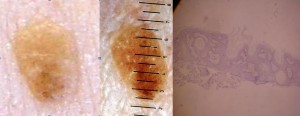

Correlations between clinical findings and histology

SK have a wide range of presentation. Clinically lesions of SK seem to evolve from clinically smooth lesions to crusty ones. In our experience detailed in the etiology section, not all smooth lesions evolve and even big keratotic lesions can continue to grow.

Reticulate type of SK are by definition Acanthotic and acanthotic SK are often reticulate. That is why we considered the Acanthotic and Reticulate type of SK as a same category (RA) and the Acantho-hyperkeratotic SK as another (AHCS).

Reticulo-acanthotic type of SK (RA): Most Sks are like this and show an acanthosis af the epidermis and a reticulate pattern. From the appearance point of view, the reticulate strands of SK keratinocytes thicken so as to be later completely acanthotic. Most SKs are in between the reticulate and acanthotic extremes and show a mix of both histological subtypes.

What we tried to do is to correlate clinical lesions with their histological lesions. We photographed lesions suggestive of SK and shaved them for histological confirmation.

Ruguous surface are more evolutive SK with a histological diagnosis of Acanthohyperkeratotic type (AHCS). This corresponds to a thick stratum corneum.

Smooth appearing young SK with a histological diagnosis in the Reticulo-acanthosic type (RA). This corresponds to a thin stratum corneum.

Clinically smooth lesions were of the reticulate and/or acanthotic type and keratotic lesions were of the acanthohyperkeratotic type. If we consider that SK have pulsed stimulations to hyperproliferate or to accumulate, we can admit that all SKs evolve from paucicellular smooth lesions of the reticulate-acanthotic type to pluricellular thickened SK of the acantho-hyperkeratotic type. These paucicellular smooth lesions arise from macular SK, considered by some a solar lentigo. No clonal SKs were detected in our study and their probable rarity does not enable us to hypothesize a relationship between the clinical and histological picture of this subtype.